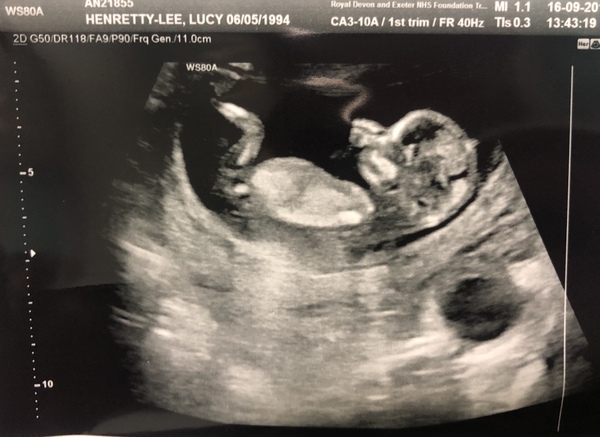

Eventrider1 · 16/09/2019 16:57

12 week scan went well today. Phew! Got pushed back by 2 days so now at 12+3 with and EDD of 27th March.

eskimod · 16/09/2019 17:26

@Eventrider1

What a lovely picture 😊 glad all is good! Congrats! X

Wow @Eventrider1 fantastic scan pic!!! Baba is so clear! Very close to my date although they will probably change it at the scan Saturday too haha.

Eventrider1 · 16/09/2019 20:55

Thank you. Baby was very wiggly and kept dancing away while they were trying to measure. Love the fact it is sucking it’s thumb as that is all I did as a baby/small child.